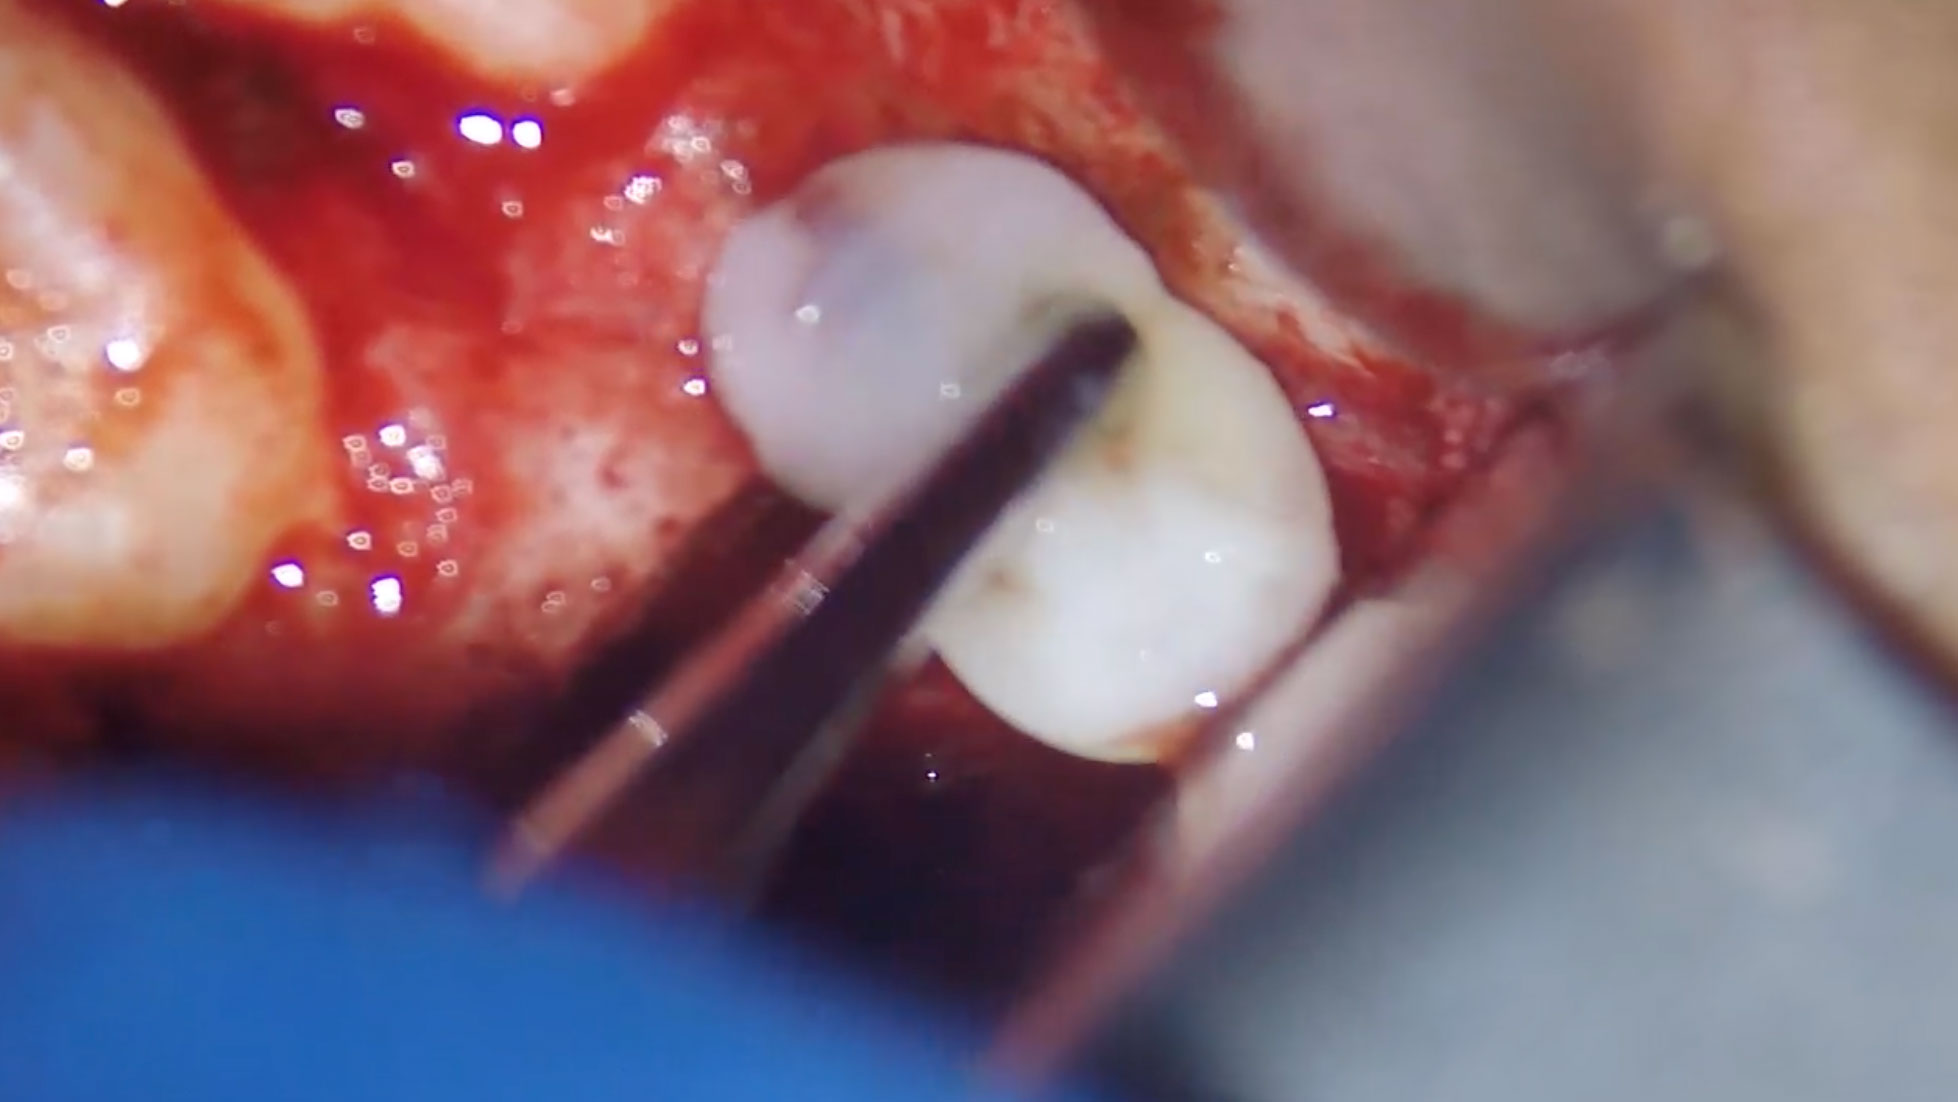

Serota-Fig-4E alternate text for this image

The unceasing innovations and iterations in dental technologies and materials has taken the sophistication of treatment modalities to an historic level. However, when we are focused on the newness, the thrill of the outcome, we fail to pay attention to the purpose of the activity. Case in point; dental implants were initially considered the gold … Read more